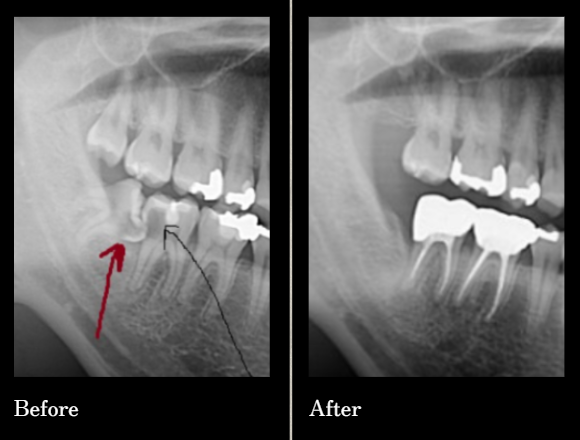

수많은 환자의 경험과 신뢰로 증명된

연세원치과 사랑니 발치입니다.

*위 케이스는 본원에서 진행 받으신 분의 동의 후 동일한 촬영 조건에서 촬영한 사진을 사용하였습니다.